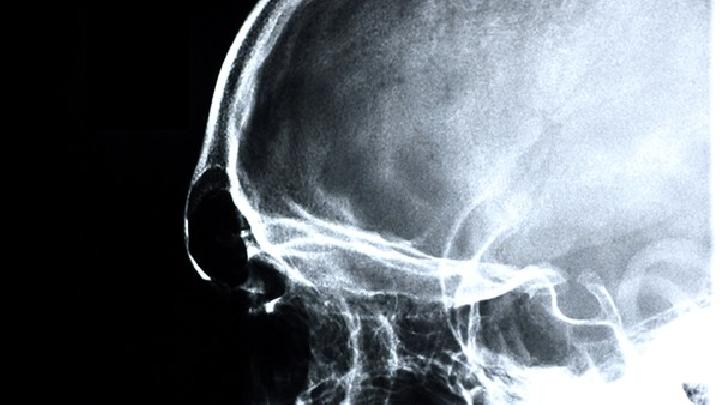

脑萎缩

脑萎缩的有效预防措施是怎样的